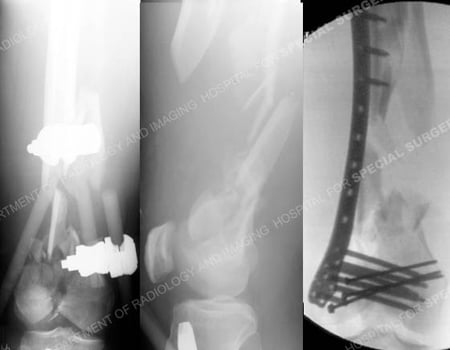

Anteroposterior (AP), and lateral radiographs (left images) revealing a supracondylar distal femur fracture (AO/OTA Type C3.3) with segmental bone loss. Intraoperative fluoroscopic AP image (right image) following fracture reduction placement of LISS plate.